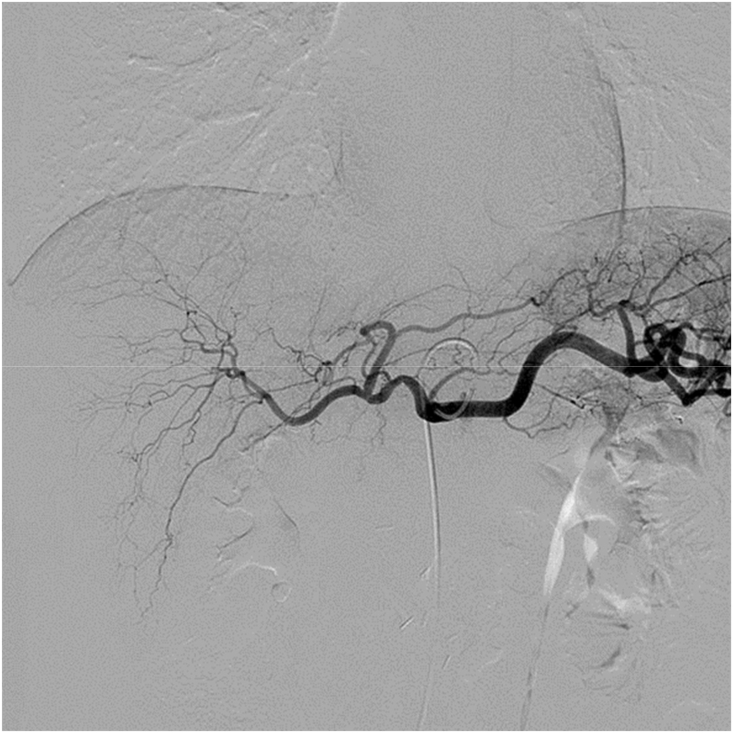

All TAI procedures were considered successful (total 85 times), withan average of 4.25 ± 1.55 procedures per patient. The treatment regimen involved 3 procedures in 10 cases, 4 procedures in 2 cases, 5 procedures in 2 cases, 7 procedures in 1 case and 8 procedures in 1 case. Five of the nine patients who did not undergo surgical resection showed a flaky, pancreatic area that showed lighter staining on superior mesenteric artery angiography (Fig. 1, Fig. 2). The remaining 15 patients showed no significant tumor staining (Fig. 3, Fig. 4).

Fig. 3.

Digital subtraction angiography (DSA) without tumor staining when angiographyat is performed at the opening of the celiac artery.

The efficacy of chemotherapy drugs depends on the drug concentration in the tumor and the contact time of the drugs within the carcinoma cells. The fibrous capsule surfacing PC challenges the penetration of chemotherapeutics. Additionally, PC often expresses high levels of multidrug resistance, resulting in rapid clearance of chemotherapeutic drugs from the tumor cells. Therefore, systemic chemotherapy does not result in a better prognosis. The principle of TAI is based on a local injection of high concentrations of drugs directly into the tumor tissue through the pancreatic artery or the parent artery segment. It increases the concentration and action time of the drugs in the tumor microenvironment to deliver toxicity to the tumor tissue and to overcome therapy resistance resulting in apoptosis and necrosis of PC cells and improving the therapeutic effect.11,14 This high local concentration of drugs affects only the pancreas with reduced side effects in all other organs.15 Thus, relative to intravenous chemotherapy, direct infusion of drugs intra-arterially leads to secondary perfusion through the portal vein and effectively kills tumor cells in the portal vein system. This either reduces or delays the occurrence of liver metastasis and improves the survival time of patients.16,17 We presume that in surgically resected patients with PC, postoperative intra-arterial infusion chemotherapy can destroy micrometastases that existed before surgery, thereby preventing the development of local recurrences and liver metastasis. In this study, patients treated with TAI had only mild fever (3/20) and nausea and vomiting (2/20) as side effects. Compared with the side effects of systemic chemotherapy and radiotherapy, these are almost negligible. During follow-up, also only four patients developed liver metastases (4/20). In fact, one patient who had undergone surgical resection showed complete remission at > 72 months of follow-up (Figs. 3 and 4).